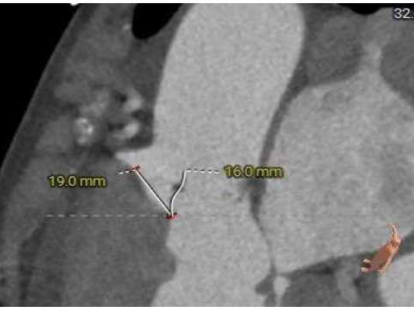

三叶式主动脉瓣,中度钙化,钙化主要分布于瓣叶附着缘及对合缘,钙化分布不均,左冠窦相对较重,右窦和无窦瓣叶对合缘处存在增厚及钙化粘连;

外周入路走行迂曲,左侧髂总存在67度锐利夹角,胸主和右侧髂总存在少量散在钙化,血管内径可,血管内壁存在钙化和不规则纤维增厚。

HU850